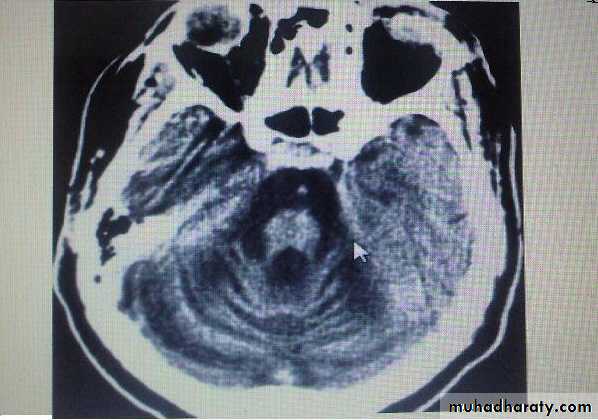

Group of heterogeneous inherited disorders characterized by slowly progressive cerebellar ataxia that affects gait early and severely and may eventually confine the patient to bed. They show considerable clinical variability .Most of them begin in adulthood. Atrophy of the cerebellum and sometimes also of the brainstem may be apparent on CT or MRI scans. Definitive diagnosis is by genetic testing. Treatment is symptomatic.Fridrich Ataxia

Alcoholic cerebellar degeneration

develop in chronic alcoholics lasting 10 or more years, probably as a result of associated nutritional deficiency. most common in men. usually start between 40 and 60 years.Degenerative changes are largely restricted to the superior vermis, usually insidious in onset & gradually progressive over weeks to months eventually reaching a stable level of deficit, Gait ataxia is a universal feature, heel-knee-shin test is +ve in about 80%. CT scan or MRI may show cerebellar atrophy. No specific treatment is available. Abstinence from alcohol, combined with adequate nutrition, leads to stabilization in most cases. All patients with this diagnosis should receive thiamine to prevent development of Wernicke encephalopathy.